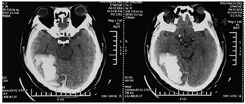

既往史:患者,男,58岁,基础疾病为高血压、高脂血症、痛风。于2014年6月12日出现突发头痛伴右侧眼眶部剧烈疼痛,当即就诊于当地医院急诊科,头颅CT示"右枕叶出血",量约90 ml,诊断为"右侧枕叶脑出血",详见图1。当地医院行"开颅血肿清除+骨瓣回纳术",术后调整脂代谢、控制血压等药物治疗后病情稳定。于2014年7月24日转入北京和睦家康复医院。入院评估,患者双眼外侧轻度视野缺损、图片识别障碍,面孔失认主要表现为患者难以认出熟悉的面孔(比如妻子和女儿),但可以通过衣服、说话声音等判断。经过4周康复治疗,患者图片和面孔识别障碍均明显改善后出院。